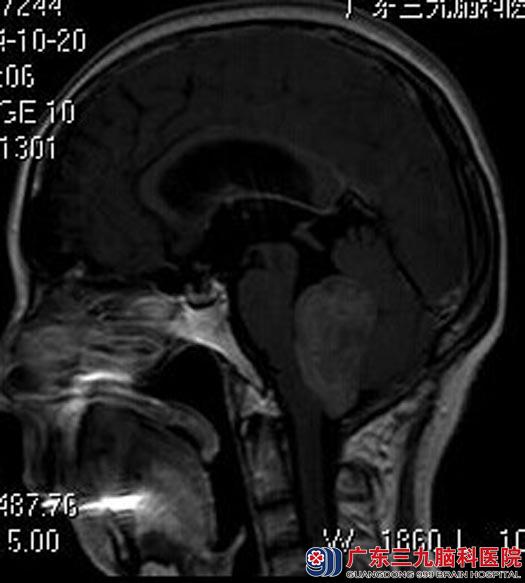

10月22日放疗后急诊行四脑室、右侧桥小脑角后颅窝复发室管膜瘤切除术,术中显微镜下暴露四脑室底部,显露肿瘤呈灰白色,质地较软,边界尚清,镜下全切除肿瘤,并完整保护舌咽神经及迷走神经,手术顺利,术后曾出现一过性声音嘶哑,经治疗未出现面瘫、后组颅神经损害等并发症,康复出院。术后病理结果:间变性室管膜瘤 WHO II级。

手术后